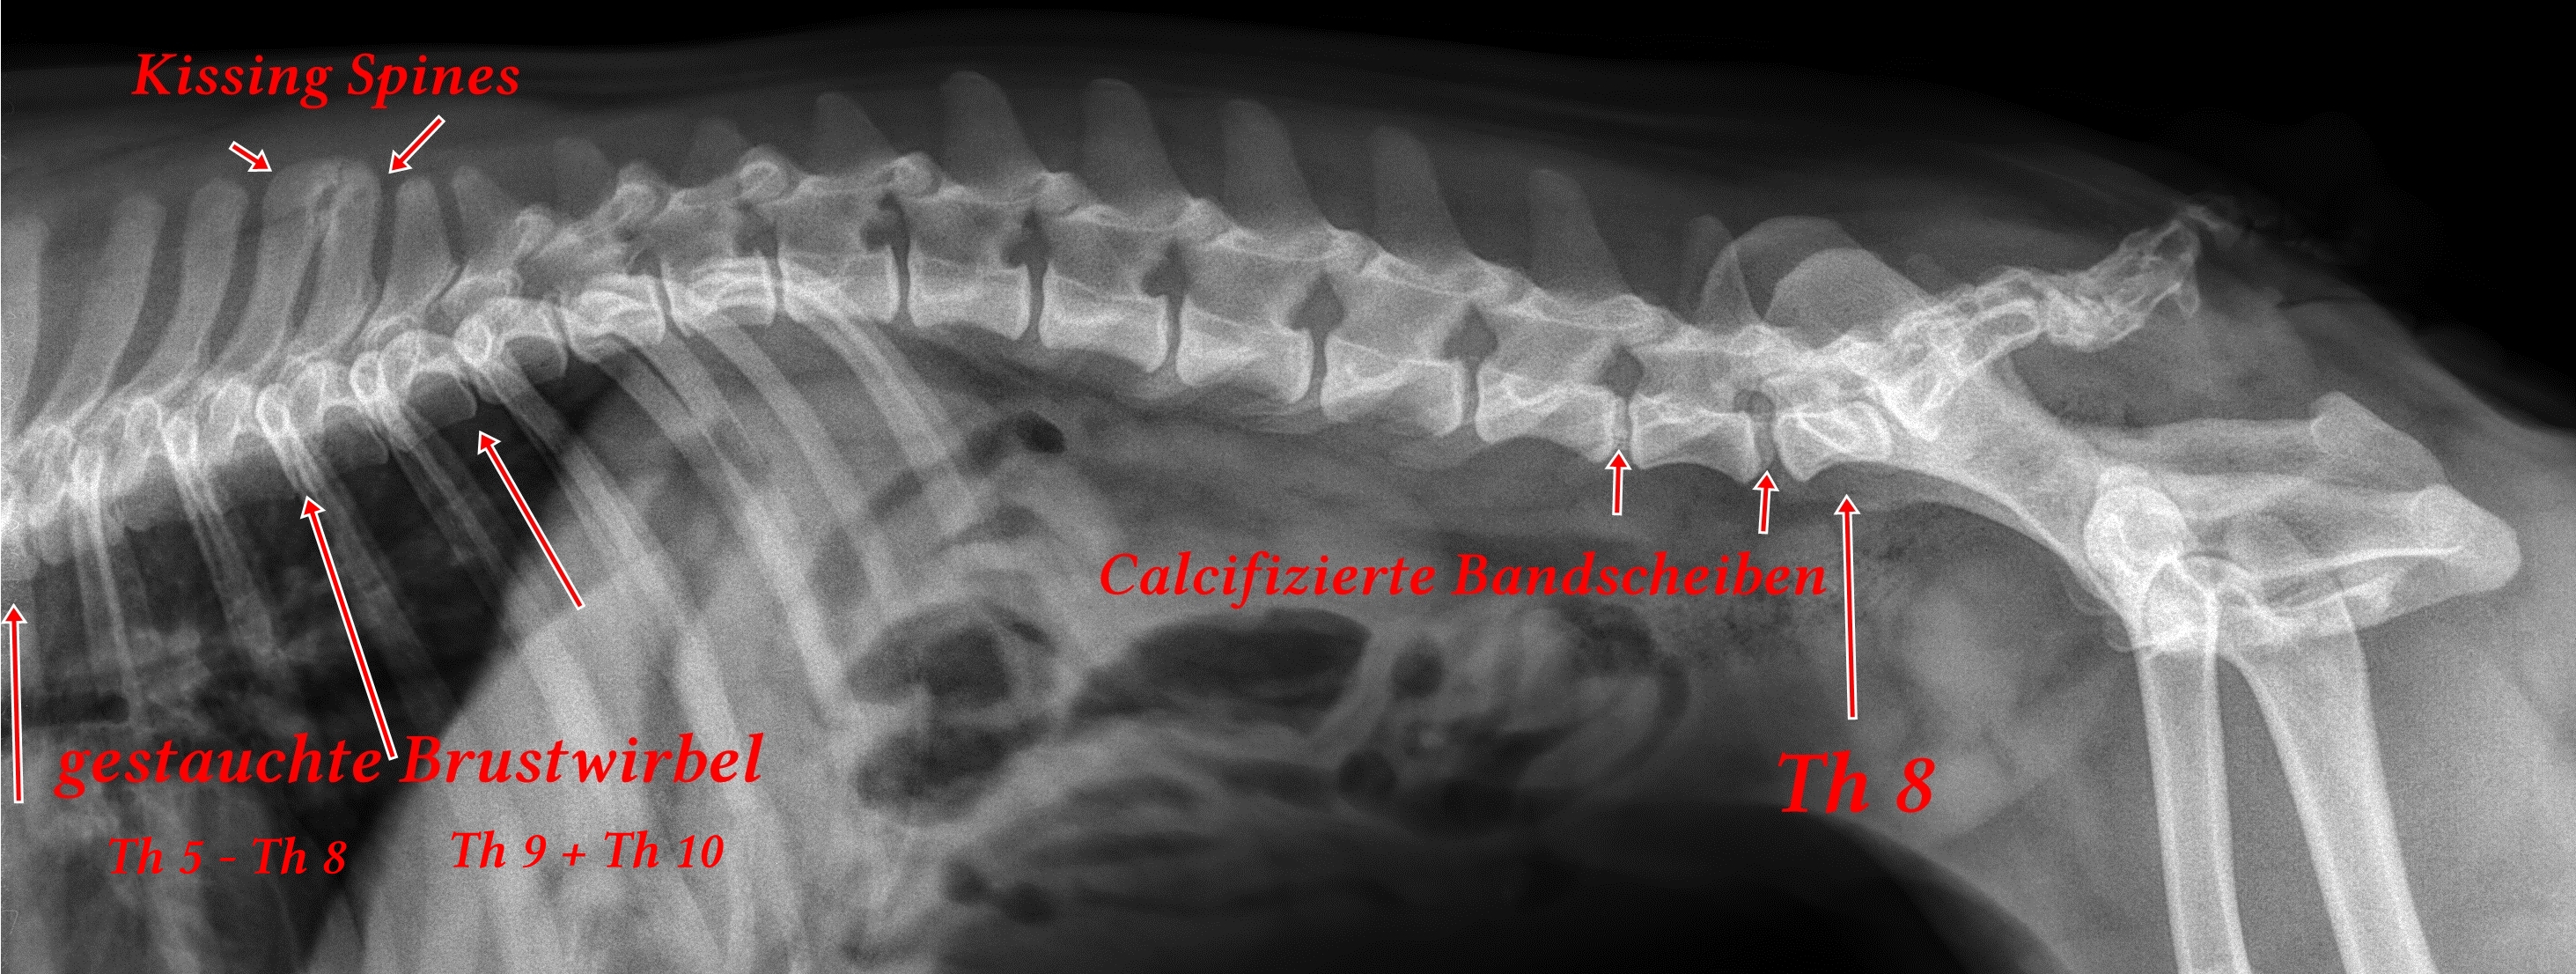

Spondylose

Boxer von Grafenwerth Spondylose